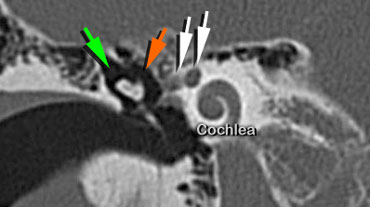

Long crus of the incus is seen connecting to the Stapes (blue arrow).Facial nerve in internal auditory canal and tympanic segment (white arrows).

Facial nerve canal

The facial nerve is seen in the internal auditory canal and entering the temporal bone (medial white arrow).

The lateral white arrow represents the tympanic segment of the facial nerve running in the facial canal and curving around the oval window niche.

At this point, the nerve runs in a horizontal plane in a posterior direction superiorly to the oval window .

The incus (orange arrow) is seen connecting to the stapes (blue arrow).

Coronal scan showing the facial nerve (white arrow) above the oval window and below the lateral semicircular canal.